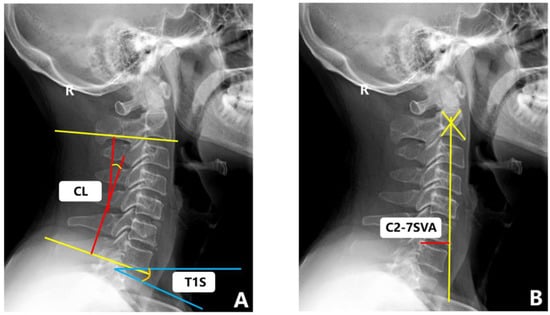

Flexion (or extension) cervical radiograph. The patient stood sideways in front of the camera frame, the head and neck were maximally flexed (or extended), the long axis of the neck was parallel to the long axis of the film, and the shoulders were drooped as far as possible. The remaining requirements were the same as those of the lateral films. All of the above images were captured by the same imaging technician. The measurement methods of the cervical sagittal parameters in the radiographs are detailed in Table 1 and Figure 4. The range of motion (ROM) was calculated as the extension minus the flexion.

Figure 4.

Sagittal radiograph of cervical spine with representative measurements. (A) C2-C7 cobb angle (CL), T1 slope (T1S). (B) C2-7SVA.